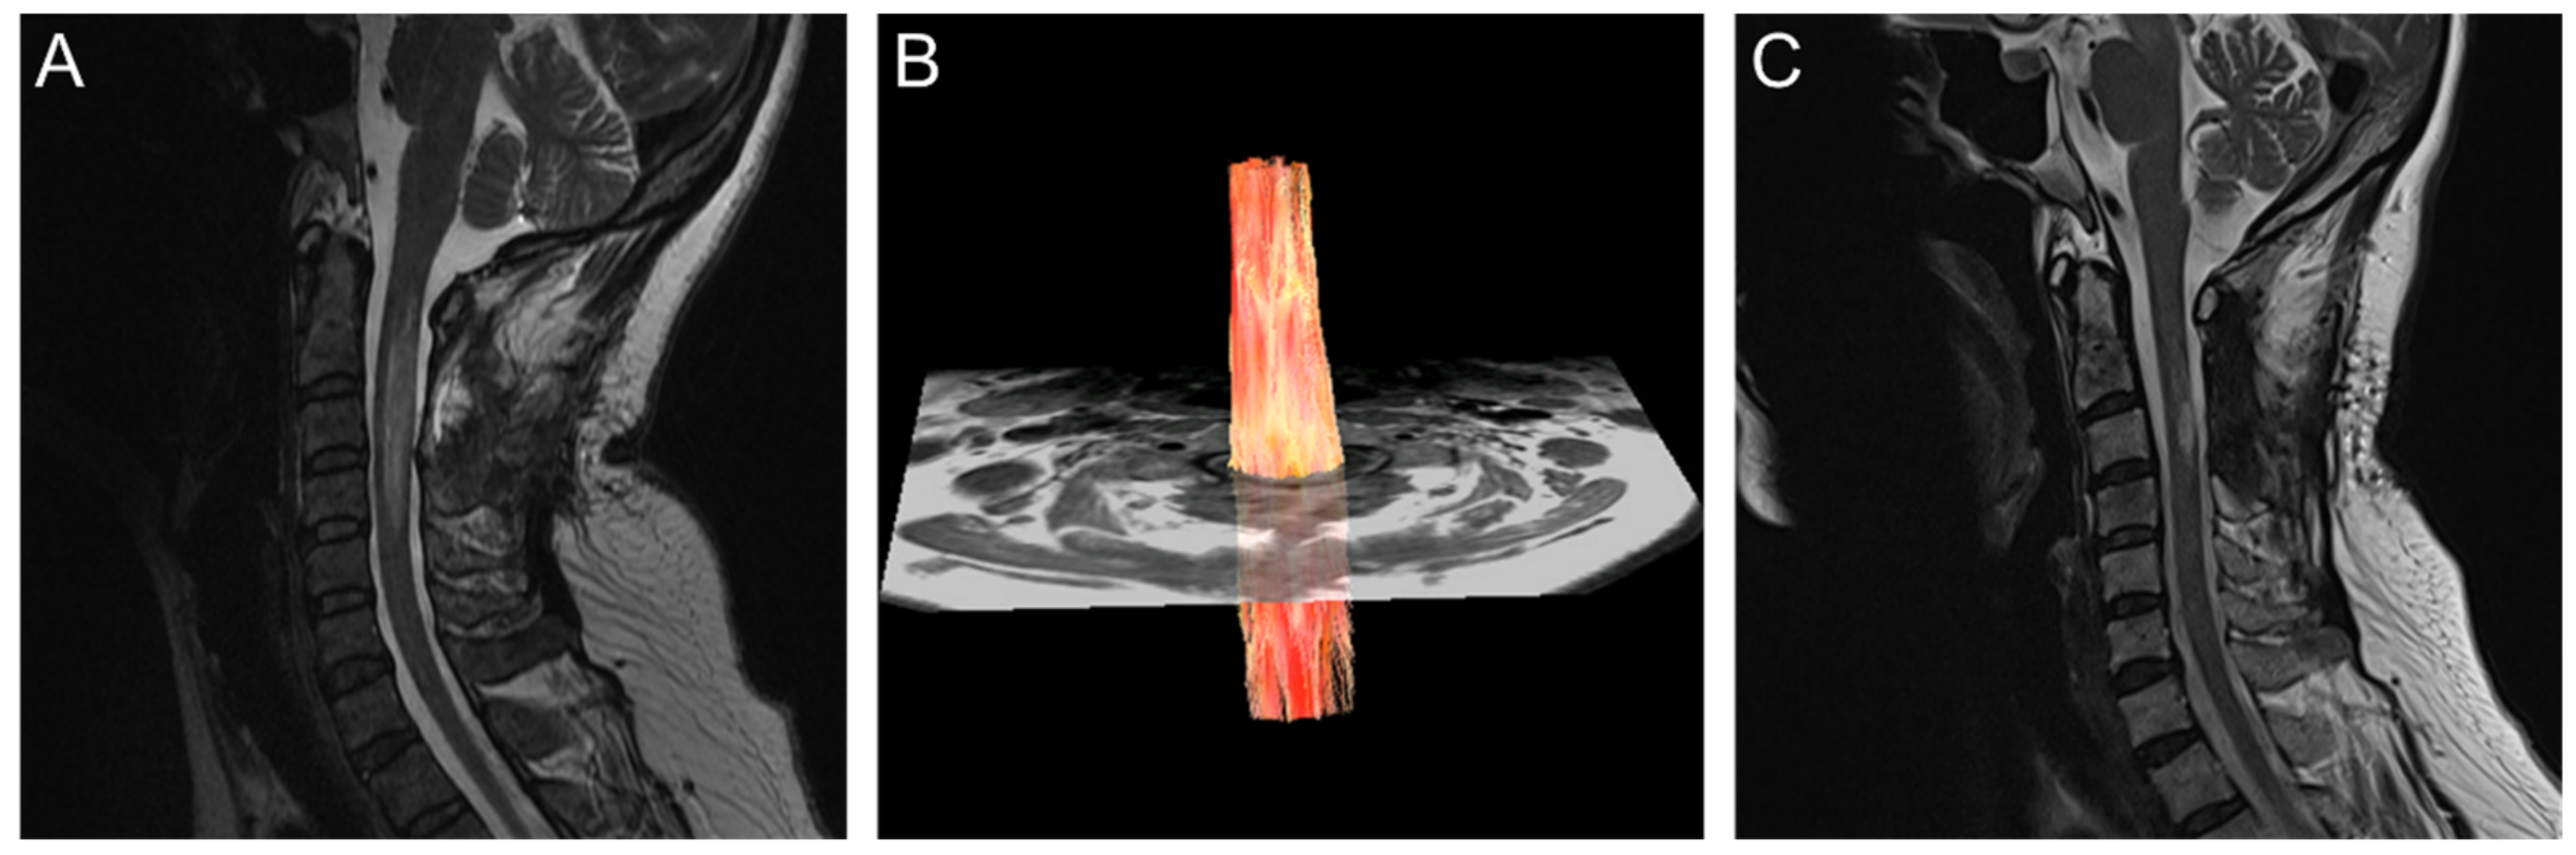

Magnetic-Resonance Diffusion-Tensor Tractography in the Diagnosis of Tumefactive Spinal-Cord Lesions in Neuromyelitis Optica

2. Case Report